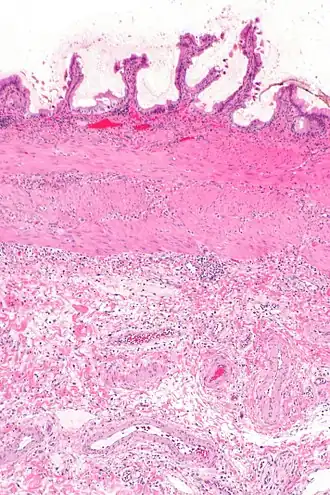

L'échographie hépatique montre une lithiase avec un aspect de cône d'ombre. Il existe un épaississement de la paroi de la vésicule biliaire, qui peut prendre un aspect feuilleté. La sonde d'échographie, passant au niveau de la vésicule, provoque la douleur (on parle donc de « Murphy échographique »). Ces signes sont très sensibles et spécifiques[4]. C'est l'examen fait en première intention.